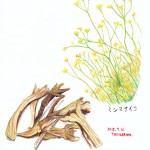

柴胡

セリ科のミシマサイコ、またはその変種の根。

性味:苦・微辛・微寒

帰経:肝・胆・心包・三焦

主な薬効と応用

①透表泄熱:外感表証の表熱に用いる

方剤例→柴葛解肌湯

②疎肝解鬱:肝鬱気滞の憂鬱・イライラ・胸脇部の張痛・月経不順などの症候時に用いる。

方剤例→四逆散

③昇挙陽気:気虚下陥の慢性下痢・脱肛・子宮下垂などに用いる。

方剤例→補中益気湯

備考:昇発の性質を持つので、虚証の気逆不降や陰虚火旺・肝陽上亢・陰虚傷津などに

用いてはならない。